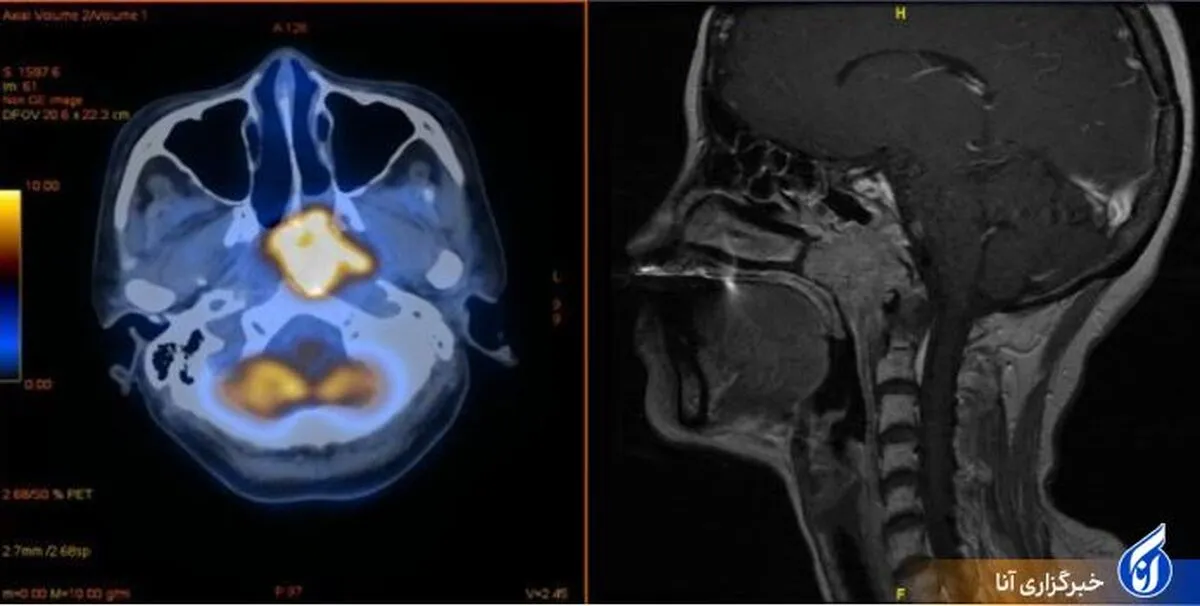

واکسیناسیون کووید-۱۹ اثربخشی درمان سرطان را بهبود می‌بخشد

سرطان نازوفارنکس یک بیماری رایج در کشور‌های جنوب شرقی آسیا است. با این حال، به نظر می‌رسد نگرانی‌ها مبنی بر اینکه این درمان ممکن است با واکسیناسیون کووید تعامل نامطلوب داشته باشد، بی اساس است.

سرطان نازوفارنکس بیماری است که در آن سلول‌های بدخیم (سرطانی) در بافت‌های نازوفارنکس تشکیل می‌شوند. نازوفارنکس قسمت بالایی گلو پشت بینی است. یک سوراخ در هر طرف نازوفارنکس به داخل گوش منتهی می‌شود.

واکسیناسیون علیه کووید همچنین پاسخ ایمنی را تحریک می‌کند که گیرنده PD-۱ را درگیر می‌کند. دکتر جیان لی از موسسه پزشکی مولکولی و ایمونولوژی تجربی (IMMEI) در بیمارستان دانشگاه بن توضیح می‌دهد: بیم آن می‌رفت که واکسن با درمان ضد PD-۱ سازگار نباشد. این خطر به ویژه در مورد سرطان نازوفارنکس، که مانند ویروس SARS Cov-۲، دستگاه تنفسی فوقانی را تحت تاثیر قرار می‌دهد، صادق است.